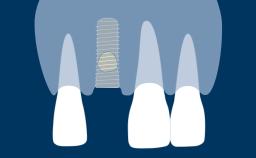

Quando um dente é extraído, o osso alveolar que suporta o dente é reabsorvido ao longo do tempo. Essa reabsorção resulta em uma redução no volume ósseo alveolar, como mostrado neste exemplo clínico de um incisivo central superior direito ausente. O osso diminuiu significativamente na largura orofacial, e isso está em conflito com o requisito fundamental da implantodontia de que os implantes são instalados na posição correta determinada pela prótese dentária. Quando o osso alveolar é reabsorvido, muitas vezes é necessário aumentá-lo para garantir que os implantes possam ser instalados corretamente e completamente incorporados ao osso. Este módulo descreverá uma técnica específica para aumento ósseo conhecida como regeneração óssea guiada ou ROG.